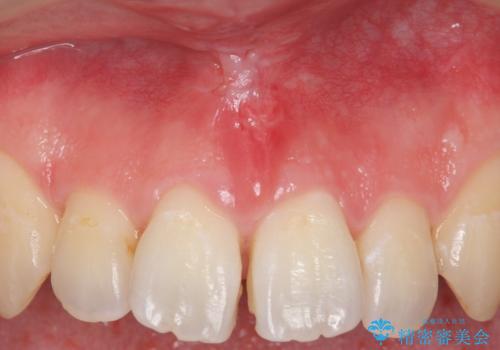

上唇小帯の切除

- 矯正治療の検査時に上唇小帯が短いことがわかり、矯正後の後戻りの予防目的で上唇小帯の切除を行いました。

上の前歯の歯と歯の間にすき間がある場合は、上唇小帯のついている位置やその長さが原因となっている場合があります。

そのままにしておくと矯正中に前歯のすき間が閉じきらなかったり、閉じたとしても後戻りをしてまたすき間ができてしまう可能性があります。

矯正の予定がなくとも、上唇小帯のつく位置が歯に近いと清掃性が悪くなるため手術で改善することをおすすめします。